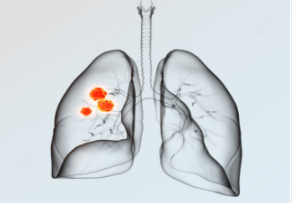

Definition: Primary bronchogenic lung cancer, commonly known as lung cancer, is the most common primary malignant tumor originating from the trachea, bronchial mucosa, small bronchi, or glands in the lungs.

Based on histopathological characteristics, lung cancer can be classified into non-small cell lung cancer (80%-85%) and small cell lung cancer (15%-20%), which has a higher degree of malignancy. Non-small cell lung cancer includes adenocarcinoma, squamous cell carcinoma, and large cell carcinoma.

Based on the location of occurrence, lung cancer can further be categorized as central lung cancer and peripheral lung cancer.

Central Lung Cancer: Refers to lung cancer originating from the bronchi above the segmental level, primarily consisting of squamous cell carcinoma and small cell lung cancer. Pathological diagnosis can typically be obtained through fiber bronchoscopy. Surgical resection of central lung cancer is challenging, and often limited to complete resection of the entire affected lung. Patients may have difficulty tolerating the procedure, and due to the advanced stage, local invasion, mediastinal lymph node metastasis, and other factors, surgical outcomes may not be ideal, with a higher risk of bone metastasis.

Peripheral Lung Cancer: Refers to lung cancer occurring below the segmental bronchi, primarily including adenocarcinoma. Pathological diagnosis is commonly obtained through percutaneous transthoracic needle biopsy guided by CT. In clinical practice, peripheral lung cancer is often asymptomatic in the early stages and is frequently detected incidentally during physical examination. If detected early, surgery is the primary treatment option, followed by adjuvant chemotherapy or targeted therapy.